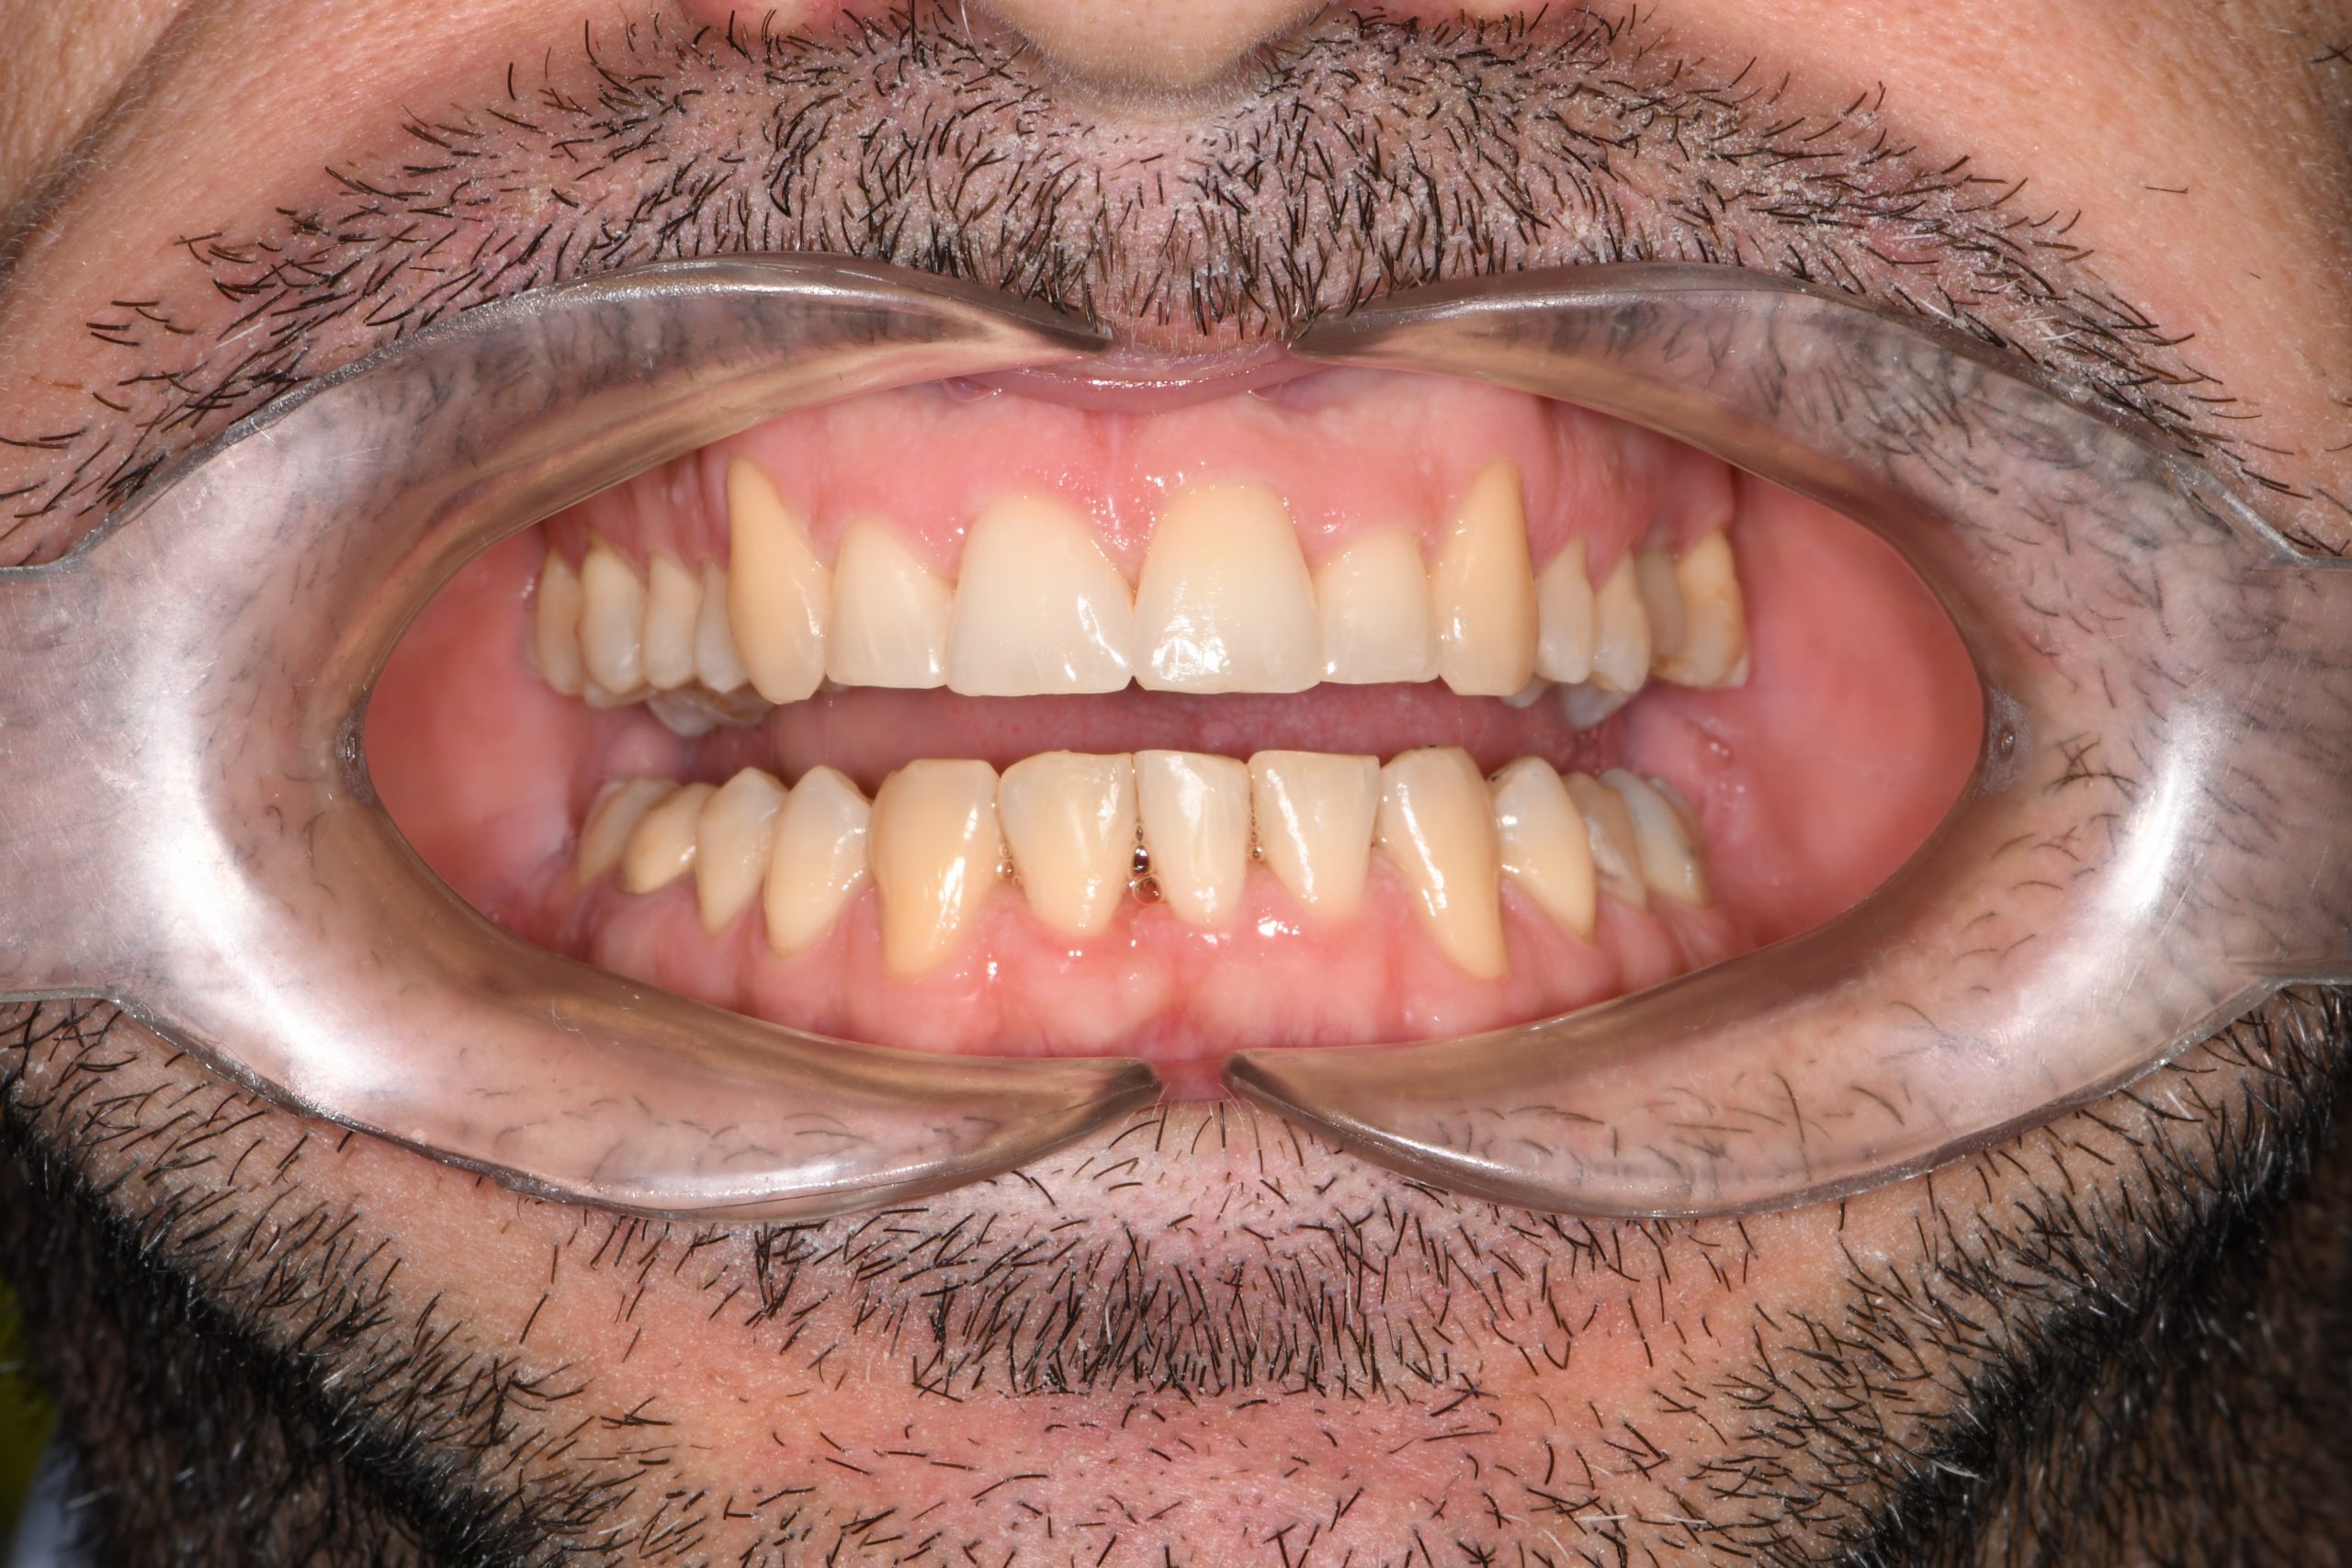

Az elmúlt évekből rengeteg szakmai referenciát tudnánk bemutatni, amelyek különböző fogszabályozási problémákat oldottak meg. Válogatva a több száz esetből, ezen az oldalon olyan képeket, információkat igyekeztünk bemutatni, amelyeknek a segítségével a jövőbeni pácienseinknek azt tudjuk üzenni: A Te fogsorod is lehet gyönyörű!

(Képeket a Pácienseink külön írásos beleegyezésével mutatjuk be!)